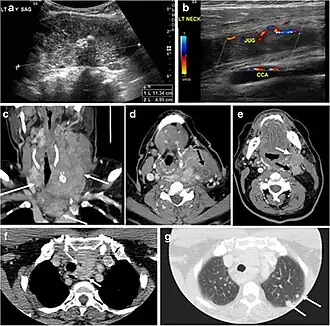

Fig. 7. A 51-year-old female patient post total thyroidectomy for PTC with elevated thyroglobulin measurement. an Axial non-enhanced CT scan of the neck at the level of the thyroid bed demonstrates a well-defined, rounded, homogenously dense soft tissue situated between the trachea and left internal jugular vein (white arrow). b Transverse ultrasound image of the neck demonstrates a well-defined, homogeneous, hypoechoic soft tissue nodule measuring 6 mm (white arrow) with no detected micro-calcifications. Biopsy showed a predominantly residual normal thyroid tissue with micro-foci of PTC.[1] -

Fig. 8. A 48-year-old male patient post total thyroidectomy with PTC recurrence. a Transverse greyscale ultrasound of the neck demonstrates a left thyroid bed heterogeneous, predominantly hypoechoic irregular lesion with calcifications (white arrow). b A spot image of iodine 123 total body scan of the neck demonstrate a focus of abnormal radiotracer uptake at the left thyroid bed (Black arrows) between the annotated markers. c Enhanced axial CT scan of the neck demonstrates an enhancing large left thyroid bed mass (white arrow) with no calcifications. The lesion exerts a mass effect on the oesophagus (black arrow) and is inseparable from the trachea.[1] -

Fig. 9. A 58-year-old male patient with persistence PTC at thyroid bed with hypervascular nodal metastasis. a–c Transverse greyscale and colour Doppler neck ultrasound demonstrate hypoehoic soft tissue in the left thyroid bed (white arrow in a). There are a heterogeneous enlarged lymph nodes at level 2 and 3 with markedly increased vascularity (white arrow in b and c). d–f Enhanced axial CT images of the neck demonstrate a 2.7 × 1.4 cm hypodense soft tissue lesion anterior to the left carotid sheath (white arrow). There are left-sided enhancing abnormal and enlarged lymph nodes at cervical level 2 and 3 (black arrows).[1]